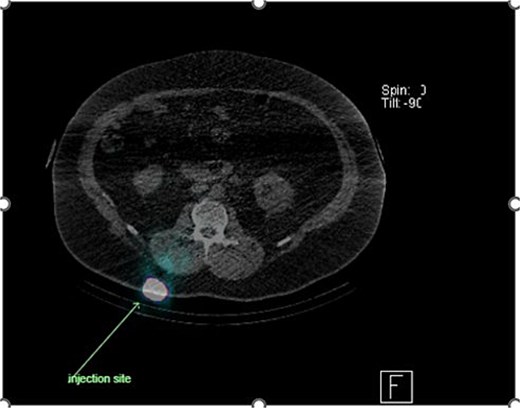

Preoperative lymphoscintigraphy was performed to detect the sentinel lymph node (Fig. 1), expecting it to be in the right inguinal region (Fig. 2). However, drainage to both the right axillary (Fig. 3) and inguinal areas was demonstrated. During surgery, a gamma camera confirmed drainage to both regions (Fig. 4). Blue dye was injected around the previous scar, and sentinel nodes were dissected guided by both blue dye and gamma camera for histopathology.

Lymphoscintigraphy showing drainage from the right lower back lesion.